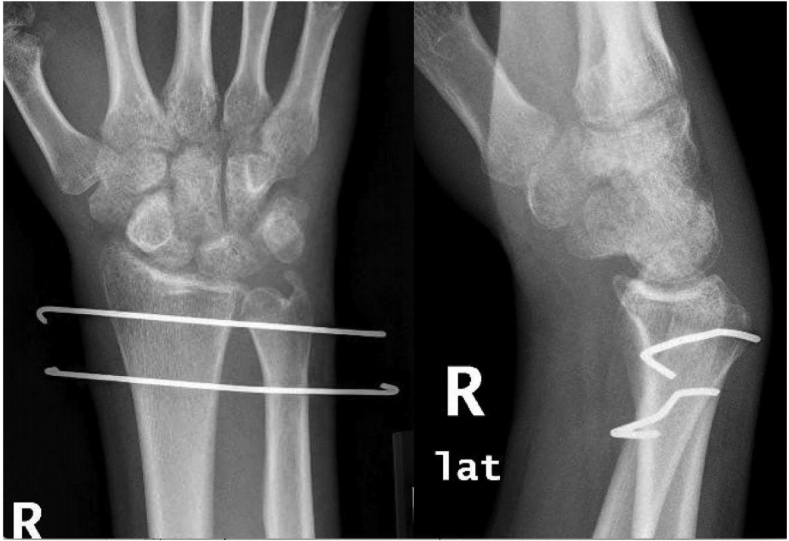

急诊科在镇静状态下尝试闭合复位,然而尝试失败,手腕被放置在临时夹板中,直到脱位可以通过手术复位。患者随后被送往手术室。尝试在全麻下闭合复位,但也失败了。DRUJ的背侧入路在第五伸肌间室上使用。关节暴露,尺骨头部掌关节脱臼,三角纤维软骨复合体(TFCC)完好无损。使用Freer升降机进行了多次复位试验,但即使在释放桡尺背侧韧带后也失败了。掌侧第二个切口用于接近尺骨腕屈肌(FCU)和趾浅屈肌(FDS)之间的关节。尺骨头部被发现穿过囊扣,并撞击桡骨的乙状切口。只有在释放掌侧囊并解除尺骨头部撞击后才可能复位。桡尺背韧带修复;然而关节不稳定,在DRUJ附近的桡骨和尺骨上使用两根克氏针使其稳定。手腕和前臂放在钳夹板上,处于中立位置(图3)。

图3. 复位后手腕的X线照片。